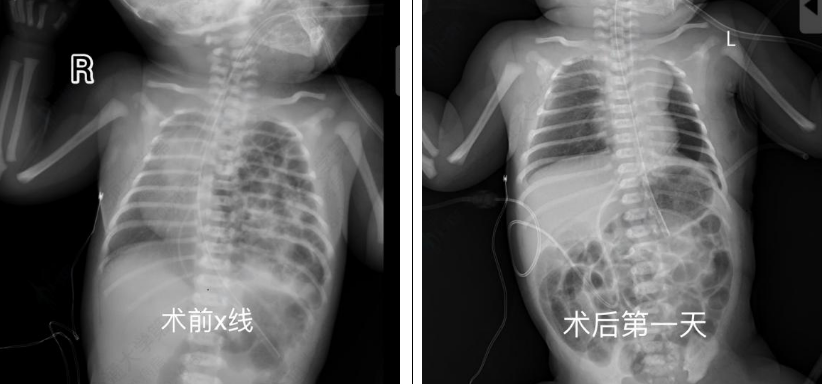

出生后24小时,患儿病情逐渐趋于稳定,但影像学提示脾脏、肠管仍大量疝入胸腔,肺组织明显压缩,有可能发生肠绞窄或感染性休克,危及患儿生命。经综合评估,依据胎儿先天性膈疝临床管理指南(2022),儿外科团队决定实施胸腔镜下膈疝修补术。

手术过程中可见脾脏及肠管几乎占据整个胸腔,造成肺组织严重受压。与传统开胸手术相比,胸腔镜手术具有创伤小、恢复快的优势,但在新生儿中操作空间极为有限,且脏器质地柔嫩,手术风险和技术要求显著提高。尤其是新生儿脾脏组织异常脆弱,稍微牵拉或触碰即可导致出血,且止血困难,因此操作需慎之又慎。在充分暴露后,曹振杰主任小心翼翼地将腹腔脏器全部还纳后,随即对膈肌缺损进行修补,每一针都精准缝合,避免出现缝隙导致再次疝入,由于缺损面积巨大,无法直接采用折叠缝合方式关闭,因此使用生物补片行加固修补。在麻醉科和手术部护理团队的精密配合下,儿外科团队成功将脏器还纳腹腔并精准修补膈肌缺损,手术顺利完成。术后患儿肺扩张逐渐恢复,呼吸功能改善,成功撤离呼吸机。目前状态良好,已顺利出院。